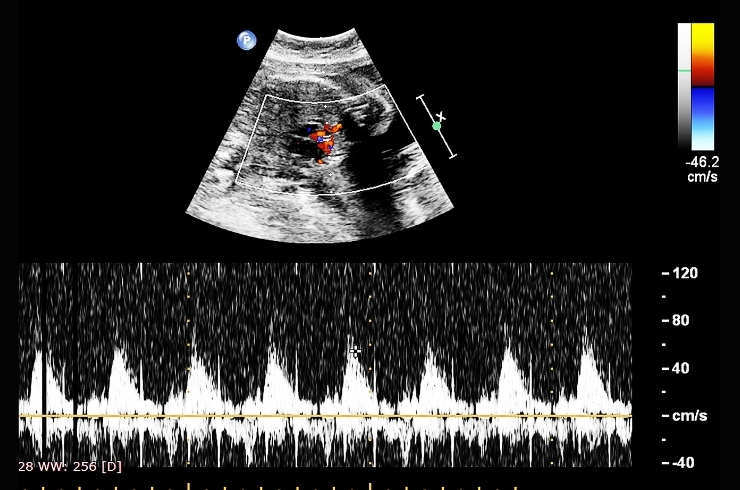

Transthoracic Echocardiography (TTE)

Non-invasive ultrasound of the heart performed through the chest wall to assess structure, function, and detect abnormalities in real time.

Fetal Echocardiography

Specialized ultrasound to evaluate an unborn baby’s heart for congenital defects, rhythm issues, and overall cardiac development in utero.